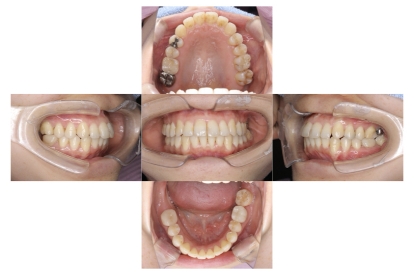

症例1

上顎前突、叢生

抜歯

ブラケット矯正

上下顎叢生、上顎前突(出っ歯、上下の前歯のガタガタ)のケースです。

装置はラビアル(上下表側)で、上顎の小臼歯を2本抜歯を行っています。抜歯したスペースを使って、上の前歯の後方移動と叢生(ガタガタ)と出っ歯の改善を行っています。下は歯と歯の間にIPR(隣接面削合)を行い、スペースを確保し、叢生の改善を行っています。

主訴 前歯のガタガタと出っ歯が気になる。

年齢・性別 47歳 女性

お住まいの地域 神奈川県川崎市

治療方針 抜歯スペースおよびIPRを利用して上前歯の叢生(ガタガタ)の改善

抜歯部位 上顎左右第一小臼歯

使用装置 ラビアル(上下表側)、顎間ゴム

治療期間 2年0か月

治療回数 15回

リテーナー クリアリテーナー

BEFORE

AFTER